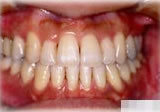

初診時年齢31歳7ヶ月。下顎側方偏位による咬合不全を主訴に来院。

顎変形と診断し、外科的処置を併用して治療。

正面 正面 正面